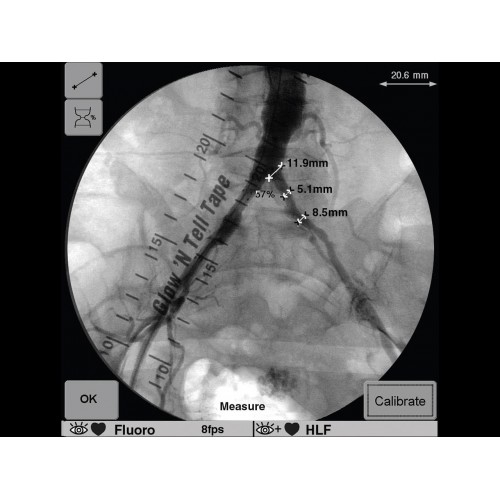

Рентген аппарат GE OEC 9900 Elite

Инновационная мобильная С-дуговая система для интраоперационной визуализации с высоким разрешением. Обеспечивает хирургов качественным изображением в реальном времени при минимальной лучевой нагрузке. Усовершенствованная эргономика позволяет легко позиционировать аппарат в условиях операционной. Поддерживает интеграцию с современными хирургическими навигационными системами.

Передовая рентгенохирургическая система GE OEC 9900 Elite представляет собой инновационное решение для проведения широкого спектра малоинвазивных вмешательств. Это оборудование премиум-класса сочетает высочайшее качество визуализации с интуитивно понятным управлением, устанавливая новые стандарты в области интраоперационной рентгеноскопии.

GE OEC 9900 Elite оснащен революционной системой визуализации, обеспечивающей кристально четкое изображение анатомических структур. Интеллектуальная система автоматически адаптирует параметры исследования под конкретную хирургическую задачу, обеспечивая оптимальный баланс между качеством изображения и лучевой нагрузкой. Особое внимание уделено удобству работы операционной бригады.

В ведущих медицинских центрах GE OEC 9900 Elite успешно применяется для проведения сложных кардиологических, нейрохирургических и ортопедических вмешательств. Система доказала свою эффективность при выполнении стентирования коронарных артерий, эмболизации сосудов головного мозга и вертебропластики. Многие учреждения отмечают повышение качества операций после внедрения этого оборудования.